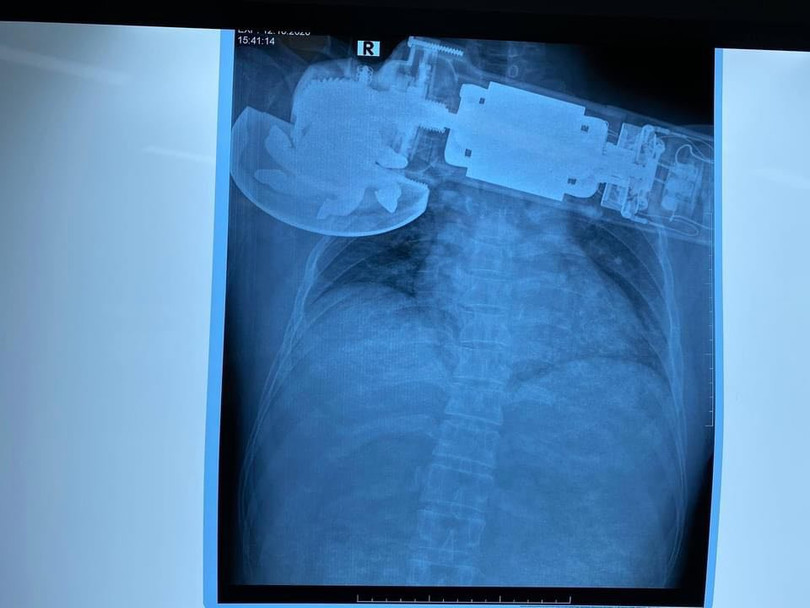

Máy chà cắm găm vào ngực phải của bệnh nhân (Ảnh: BVCC)

Theo Bệnh viện Trung ương Quân đội 108, nữ bệnh nhân sống ở Bắc Ninh vào viện trong tình trạng bị máy chà văng, cắm găm vào ngực phải, vết thương không chảy máu, không khó thở, huyết động ổn. Theo lời kể của bệnh nhân, khi đang làm việc chị bất ngờ bị máy chà văng vào áo rồi cuốn vào ngực phải.

Sau khi thăm khám, các bác sĩ thấy máy chà đã găm sâu vào thành ngực phải của bệnh nhân ở sát bờ dưới xương, bờ mép vết thương nham nhở, phần mềm thành ngực bị cuốn vào trong máy chà gây khuyết hổng phần mềm, mất da và bầm dập da quanh tổn thương. Ngay lập tức, bệnh nhân được chỉ định mổ cấp cứu xử trí vết thương.